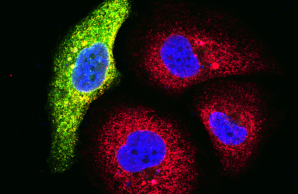

Project 3 utilizes high-throughput sequencing technologies to discover novel disease genes for primary early-onset low bone mineral density disorders. For each newly identified monogenic disease gene, specific combinations of clinical features, osteologic parameters, immunologic and/or metabolic changes in affected individuals will be identified. Functional studies are performed to confirm the pathogenicity of the genetic variants and to investigate the pathomechanism.

Project 4: Molecular bases of non-classical osteogenesis imperfecta

Project 5 is focused on the investigation of hypophosphatasia, a genetic disease that leads to mineralization disorders and reduced bone mass, among other symptoms. Genotype-phenotype correlations, novel model systems and therapeutic approaches as well as previously unknown pathomechanisms will be investigated.

Project 6: Molecular analysis of the bidirectional crosstalk between bone and lipid metabolism

Central Project 1: Generation of human induced pluripotent stem cells

CP1 will establish human in vitro disease models to advance understanding of early-onset low BMD mechanisms